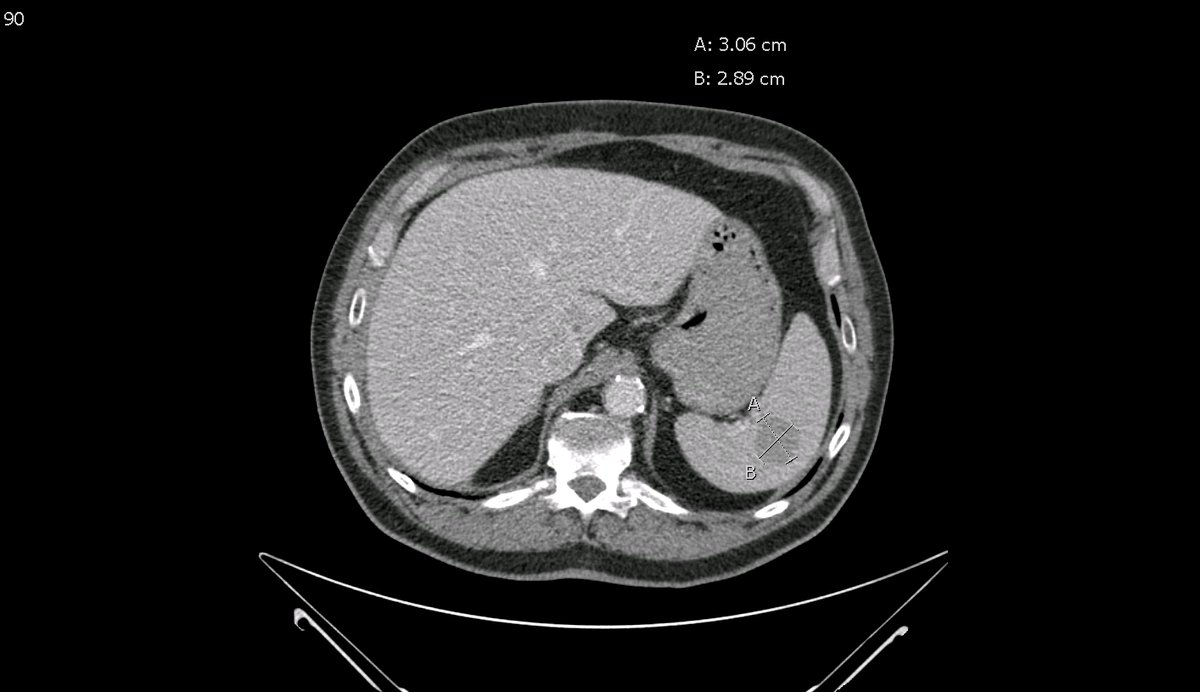

New study @AnnalsofIM bit.ly/2Km3KYu by @DrTalenfeld @WeillCornell: Percutaneous ablation for T1a #renalcancer has similar 5-year survival rates to radical nephrectomy but with far fewer 30-day complications and less #kidneyfailure.